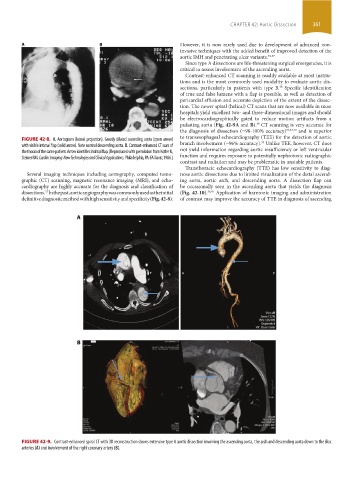

FIGURE 42-8. A. Aortogram (lateral projection). Grossly dilated ascending aorta (open arrow) to transesophageal echocardiography (TEE) for the detection of aortic

with visible intimal flap (solid arrow). Note normal descending aorta. B. Contrast-enhanced CT scan of branch involvement (̴96% accuracy). Unlike TEE, however, CT does

the thorax of the same patient. Arrow identifies intimal flap. (Reproduced with permission from Kotler N, not yield information regarding aortic insufficiency or left ventricular

Steiner RM. Cardiac Imaging: New Technologies and Clinical Applications. Philadelphia, PA: FA Davis; 1986.) function and requires exposure to potentially nephrotoxic radiographic

FIGURE 42-9. Contrast-enhanced spiral CT with 3D reconstruction shows extensive type A aortic dissection involving the ascending aorta, the arch and descending aorta down to the iliac

arteries (A) and involvement of the right coronary artery (B).